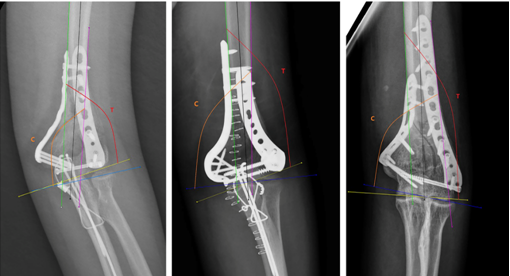

为了更好地预防创伤性肘关节僵硬,该研究针对肱骨髁间骨折术后即刻的肘关节正位X线片进行了影像学测量,基于既往关于TCI(滑车肱骨小头指数)的研究做出改良并提出了modified TCI的测量方法,以桡骨头作为“肱骨小头线”的间接测量基准线,通过分别计算“滑车线”和基准线与肱骨干中心轴或内侧皮质线或外侧皮质线的角度比值,对肱骨远端内侧柱的复位情况进行细致的评估。随后本课题组将影像学测量指标与临床指标作为整体,针对术后是否出现肘关节僵硬这一结局指标进行危险因素分析。

mTCI测量方法示例(详见原文)